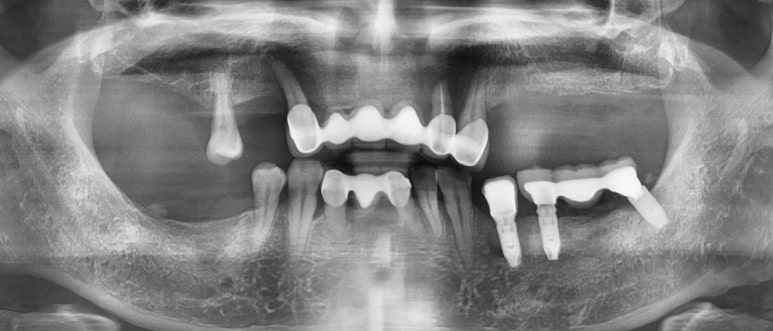

위의 엑스레이 사진은 처음에 오셨을 때의 엑스레이 사진입니다.

위쪽에 큰 어금니는 하나도 없고 앞니로만 식사를 하는 상태였습니다.

앞니 6개 중 3개만 진짜 치아이고 브릿지를 오래전에 하신 상태인데

앞니로만 식사를 할 수밖에 없다보니 앞니도 망가져서 아주 많이 흔들흔들 흔들리는 상태여서

저희 치과에 내원하게 되었습니다.

지금까지 서울 시청역 연세예감치과에서

측방 상악동뼈이식 (상악동 거상술)을 포함해

내비게이션임플란트로 상악 전체임플란트, 하악 어금니 임플란트를 시행한 케이스

를 소개해 드렸습니다 ^^